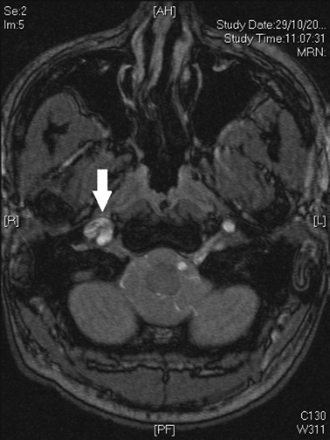

[Figure caption and citation for the preceding image starts]: MRI of carotid artery. The arrow shows narrowing of the lumen of the carotid artery caused by intramural haematomaUsed with permission from BMJ Case Reports 2012; doi:10.1136/bcr.01.2012.5636 [Citation ends].